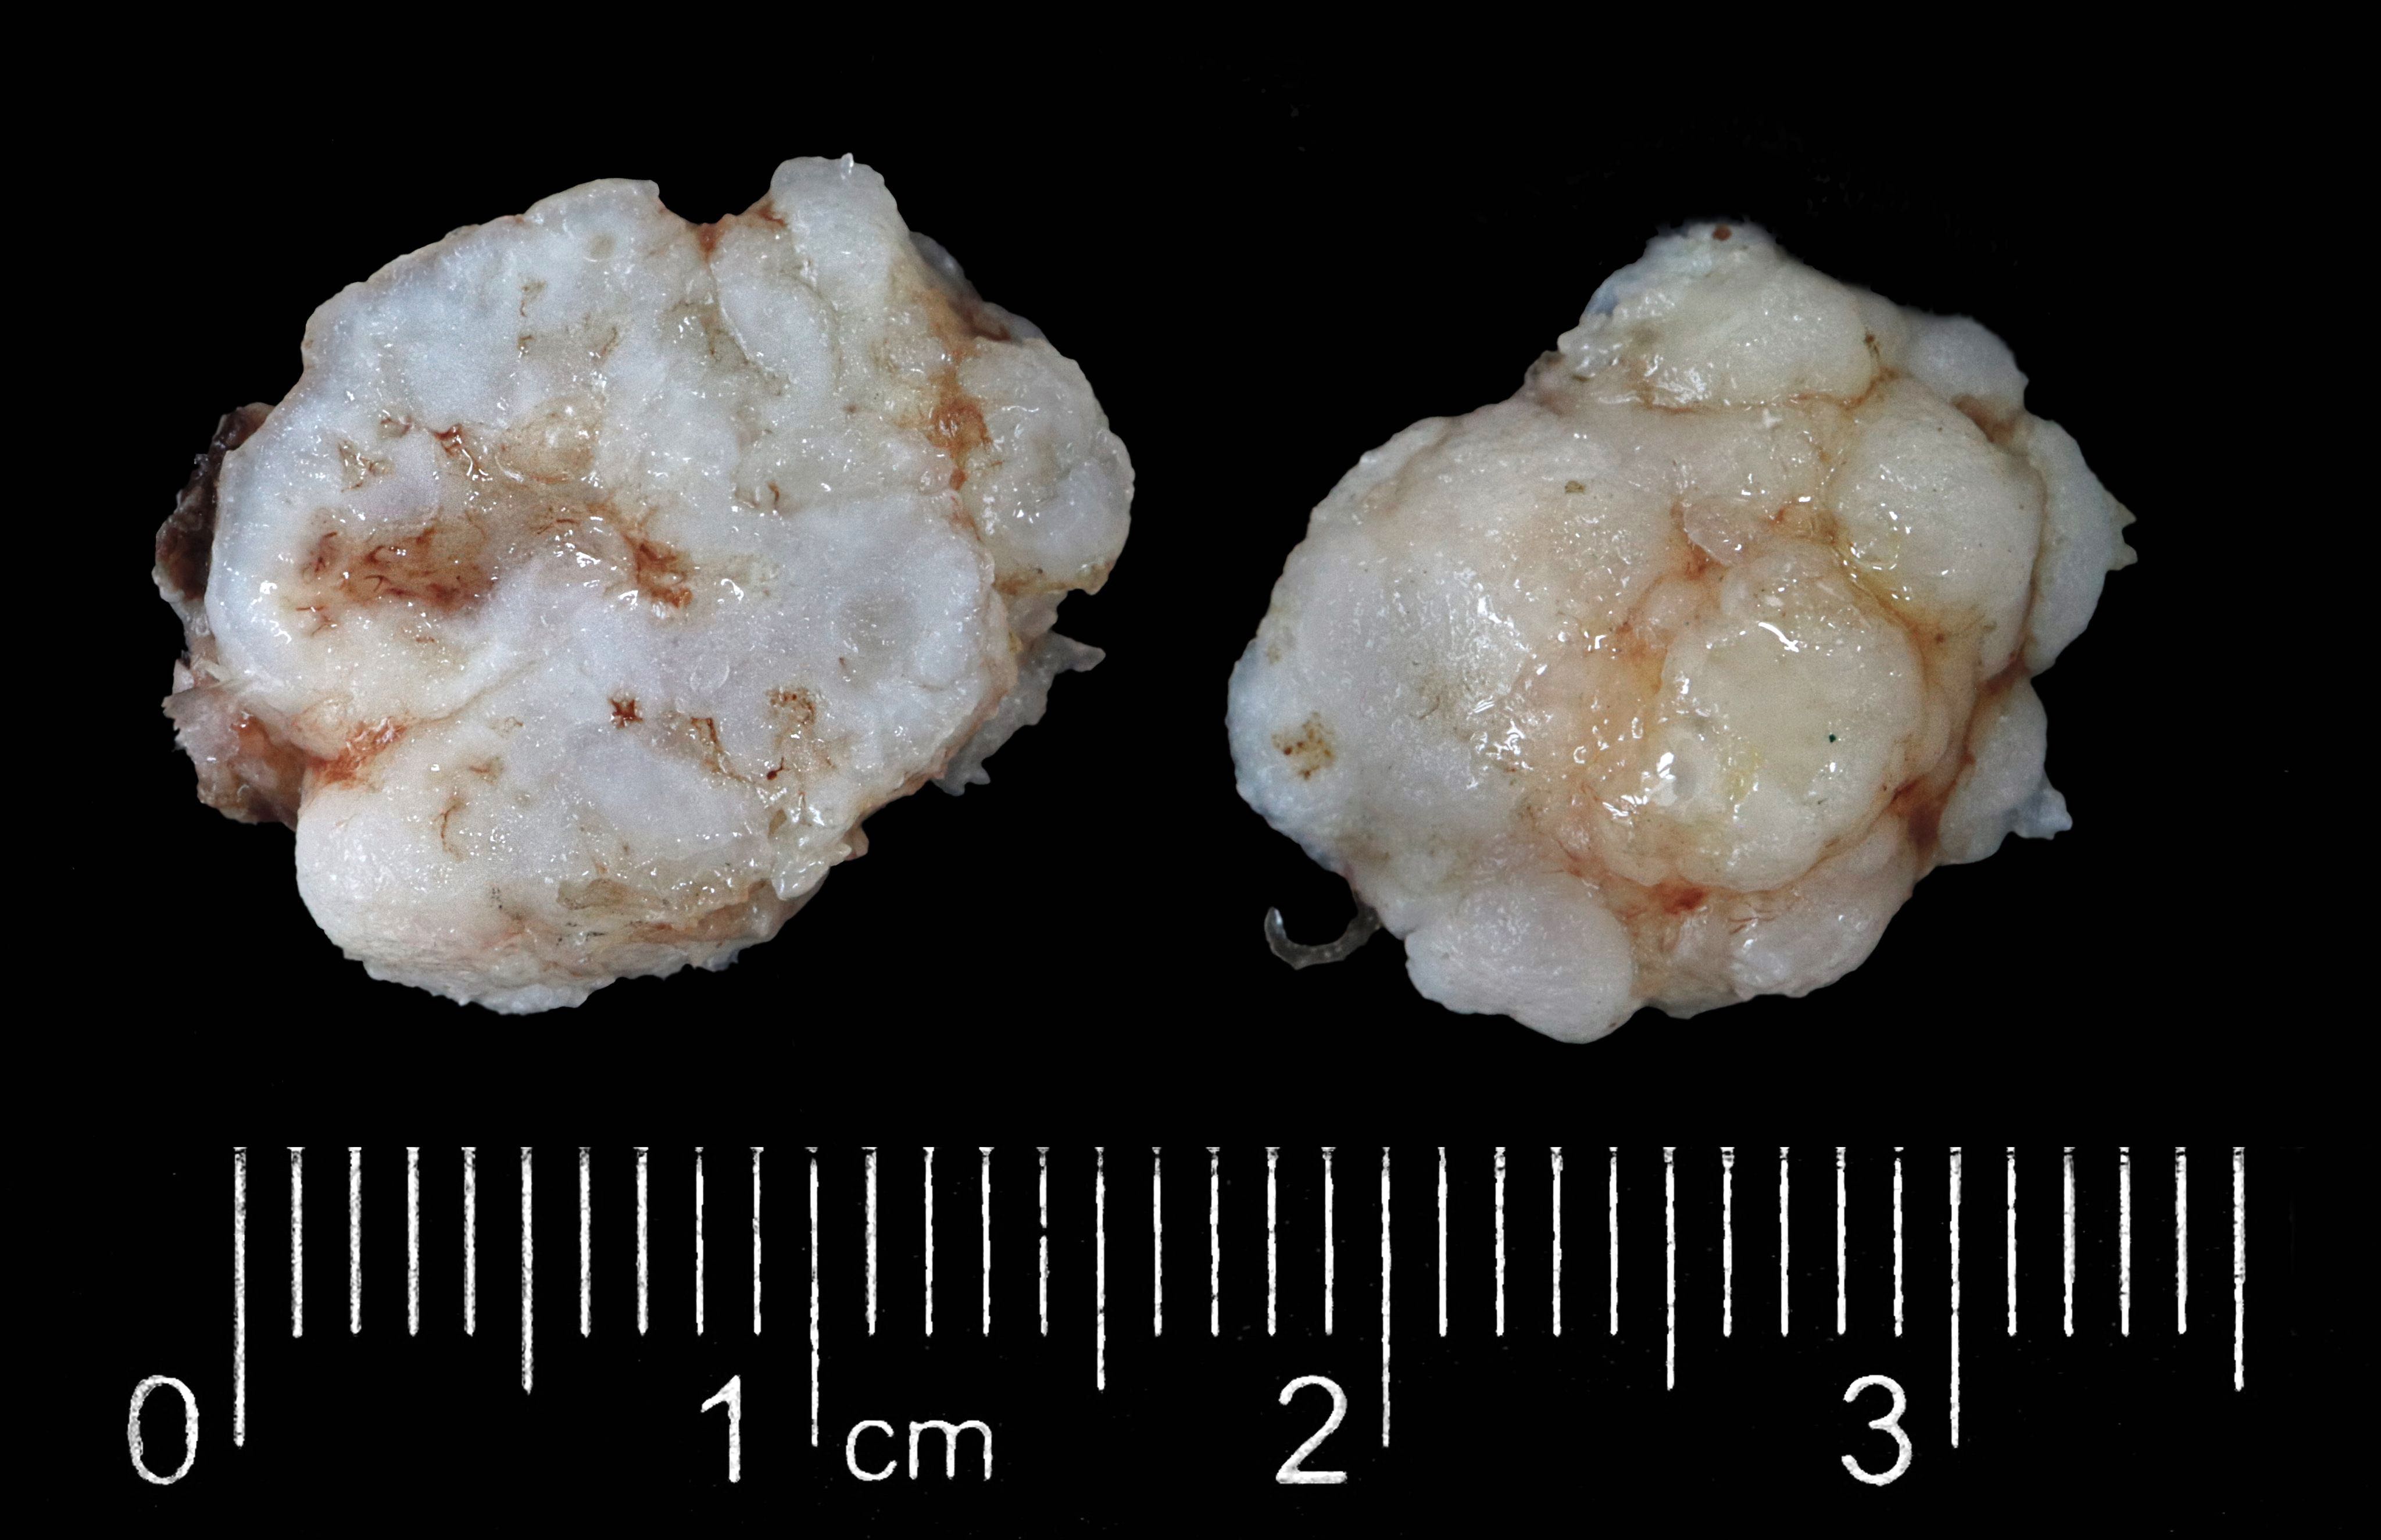

Gross description

- Pale, firm, round to multilobulated, well circumscribed nodule (most are < 4 cm in diameter)

- Endobronchial hamartoma manifests as yellow to gray sessile polyps of large airways

- References: Mayo Clin Proc 1996;71:14, Thorax 1987;42:790

Gross images